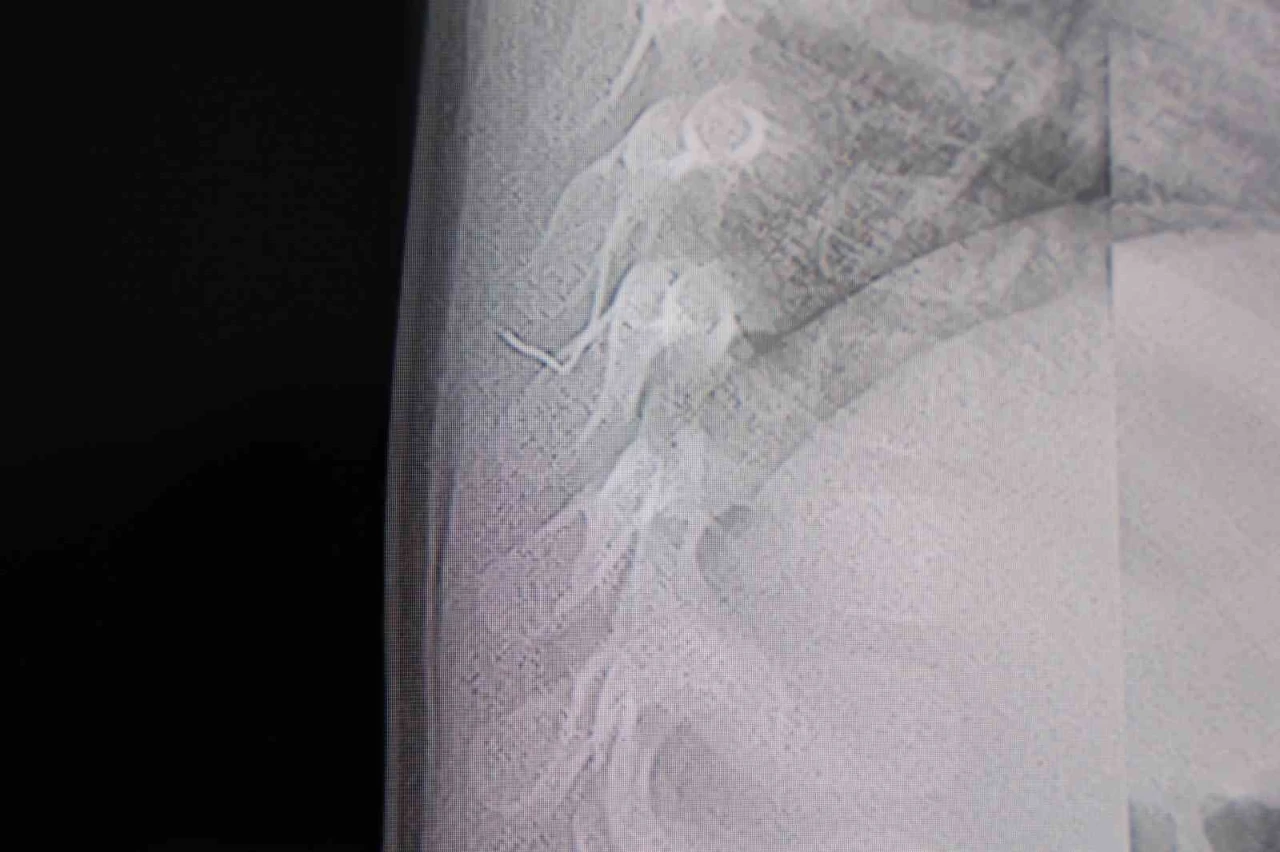

Kahramanmaraş’ta sırt üstü yatmak istemeyen, yatırıldığında ağlama ve huzursuzluğu nedeniyle hastaneye götürülen bir yaşındaki bebeğin sırtından akciğer zarına doğru ilerleyen 2 santimetrelik zımba teli çıktı.

Alınan bilgiye göre, Kahramanmaraş’ta farklı ortopedi, çocuk cerrahisi ve beyin cerrahisi kliniklerine başvurusu yapılan bir yaşındaki bebeğin, sırt bölgesinde yabancı bir cisim olduğu ancak müdahalenin zor olduğu ve 8 yaşına kadar beklenmesi gerektiği bildirildi. Aile, bebekleri için son olarak HG Hospital’e başvurdu. HG Hospital Beyin ve Sinir Cerrahisi Uzmanı Prof. Dr. İdris Altun tarafından yapılan tetkiklerde, yabancı cismin cilt altında, omurilik kanalına yakın bir bölgede olduğu ve akciğer zarına doğru ilerlediği belirlendi. Hasta, genel anesteziye alınmadan, lokal anestezi ve sedasyon eşliğinde ameliyata alındı. Yapılan müdahalede yabancı cisim tamamen çıkarıldı. Çıkarılan cismin, ince zımba teline benzer metal bir tel olduğu ve yaklaşık 2 santimetre uzunluğunda bulunduğu tespit edildi. Hasta, aynı gün taburcu edildi. "Akciğer zarına doğru ilerleyen bir yabancı cisim tespit ettik"

Konuya ilişkin açıklama yapan Prof. Dr. İdris Altun, "Sırtında yabancı bir cisim olduğu söylenmiş ancak çıkarılamayacağı ve 8 yaşına kadar beklenmesi gerektiği ifade edilmişti. Bize başvurduğunda yaptığımız tetkiklerde, cilt altında, omurilik kanalına çok yakın ve akciğer zarına doğru ilerleyen bir yabancı cisim tespit ettik. Hastamızı tamamen uyutmadan, lokal anestezi ve sedasyon eşliğinde müdahale ederek lezyonu tamamen çıkardık. Çıkardığımız cismin ince zımba teline benzer, yaklaşık 2 santimetre uzunluğunda metal bir tel olduğunu gördük. Bu yabancı cisim alınmasaydı, bölgede enfeksiyon gelişebilirdi. Enfeksiyon sonucu omurilik kanalında ciddi hasarlar oluşabilir, çocuk büyüdükçe cismin hareket etmesine bağlı olarak omurilikte zedelenmeler meydana gelebilirdi. Ayrıca yana doğru ilerleyerek akciğer zarına ve akciğere batma riski vardı. Bu da enfeksiyona ve ilerleyen süreçte tümörle karışabilecek tablolara neden olabilirdi. Şu an hastamız gayet sağlıklı. Gerekli kontrolleri yaptık ve aynı gün taburcu ettik" dedi.